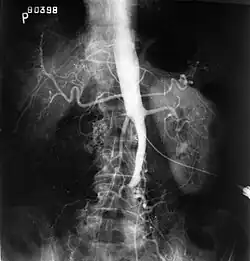

![]() Obraz angiograficzny zespołu Leriche’a | |

Zespół Leriche’a (niedrożność aortalno-biodrowa) – zespół objawów spowodowanych zwężeniem lub niedrożnością końcowego odcinka aorty brzusznej i/lub tętnic biodrowych.